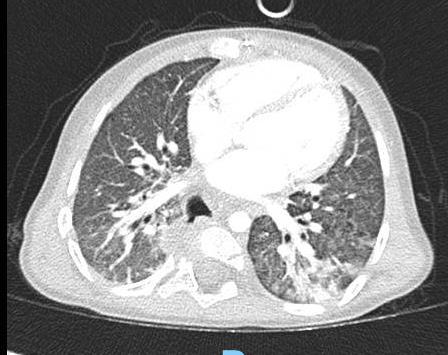

Acute Pediatric COVID-19: CT

21 Imaging of Covid 19 infection in children

3 Phases

Early: "Halo" sign

Local infection

Progressive: Diffuse GGO

Developed: Consolidation

Surr vasc congestion

Inflammation - adj alveoli

Alveoli fill with fluid/cells